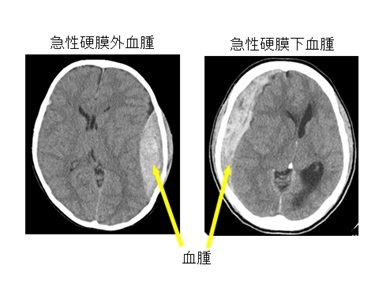

交通事故や転落事故などで頭部に衝撃を受けた場合、皮膚に傷ができます。衝撃が強ければ頭蓋骨、脳実質(頭蓋内)にまで衝撃が加わります。頭蓋内の損傷の種類には、脳への直接的な損傷(脳挫傷、外傷性脳出血)、頭蓋内血管の損傷(外傷性くも膜下出血、急性硬膜下血腫、急性硬膜外血腫、慢性硬膜下血腫)、回転性の外力による軸索(じくさく)の断裂(びまん性軸索損傷)、などがあります。これらの病態が複合して生じる場合もありますし、頭部のみならず全身の骨や内臓の外傷を合併している場合もあります。